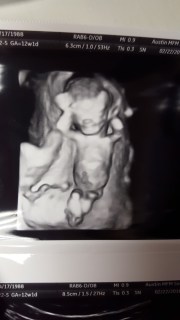

Our appointment yesterday went great! Since baby was ready to be busy and move around a lot, we got to watch on the ultrasound screen for what felt like close to 45 minutes, waiting for baby to get in the right positions for certain measurements! We didn’t mind at all ๐ We got to watch baby flip over, moved arms and hands, kick legs, ans wiggle around!We took video of the screen so I will upload that soon. She even took the 3d/4d (? I’m not really sure what it’s called) pictures! They said there is no way to tell gender from the ultrasound this early, and that’s what we expected her to say.

Here are some pictures from yesterday! Baby is laid back and hanging out in one. ๐ And thank you for the continued prayers!